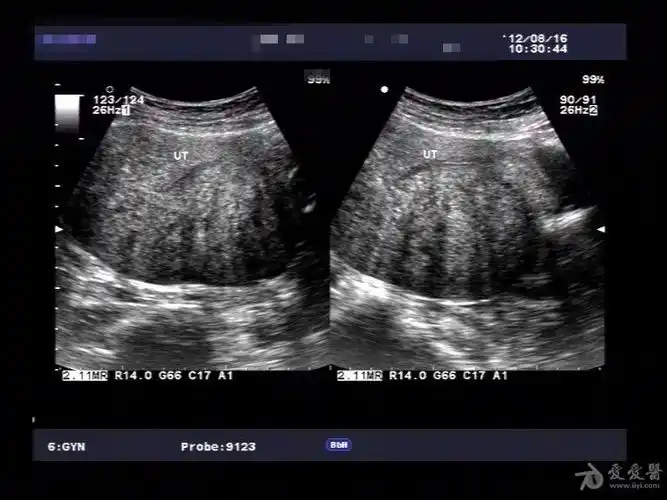

超声微课堂子宫内膜异位症子宫腺肌病

子宫腺肌症

典型病例子宫腺肌症一